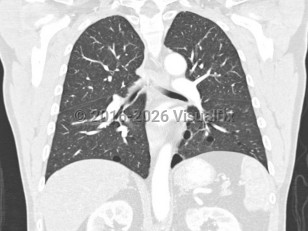

- Multiple lung cysts: bilateral basally located lung cysts with no other apparent cause, with or without spontaneous primary pneumothorax.

Approximately 80% of patients develop pulmonary cysts, which can be numerous and bilateral. They commonly affect the base of the lungs. They typically develop between the ages of 30 and 40 but have been described from ages 20-85. BHD patients are at 50-fold increased risk of spontaneous pneumothorax, with approximately 24% of those with pulmonary cysts developing spontaneous pneumothoraces at an average age of 38 years (range: 22-71 years). FLCN-mutation carriers have developed pneumothoraces as early as age 7.